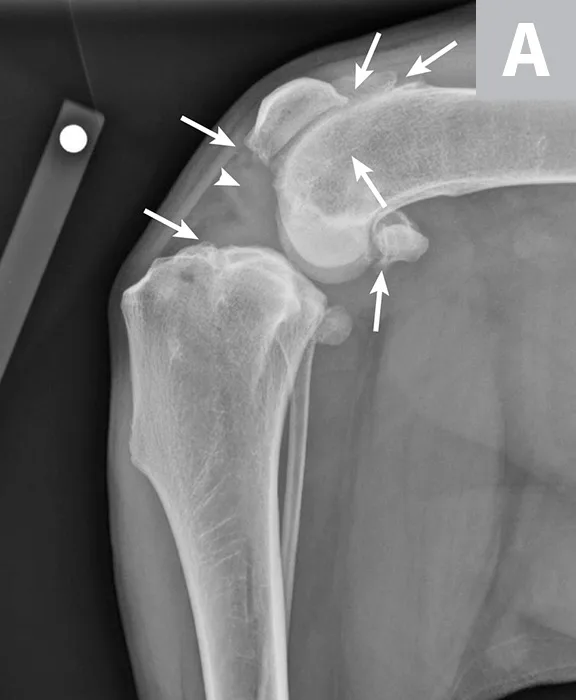

FIGURE 2

Mediolateral (A) and craniocaudal (B) radiograph projections of a 3-year-old spayed mastiff with right CCL rupture and medial meniscal tear. Osteophytes are present on the femoral condyles, patella, fabellae, and tibial plateau (arrows). There is increased soft tissue opacity in the joint space consistent with joint effusion (arrowhead). In addition, there is cranial displacement of the tibia relative to the femur on the lateral projection. These signs combined are consistent with CCL rupture.